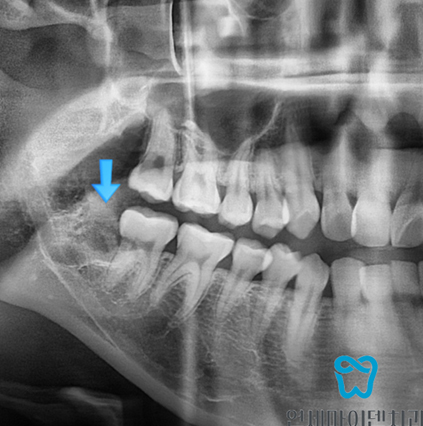

엑스레이 상으로는 매복사랑니가 보였는데 이렇게 구강내 사진을 찍어봤을 땐 안보이시죠?

끝 어금니 뒤쪽으로 완전히 매복되어 있는 사랑니입니다.

보시니까 어떠세요? 아예 사랑니 뿌리가 신경과 맞닿아 있는 것 같습니다.

앞으로 볼 땐 마치 매복사랑니가 신경과 닿아 있고 겹쳐져 있는 것으로 보이지만,,,,

보이시나요? 원래 매복사랑니가 있던 자리.

오른쪽, 왼쪽 매복사랑니 발치를 신경 손상 없이 무사히 잘 끝냈고,